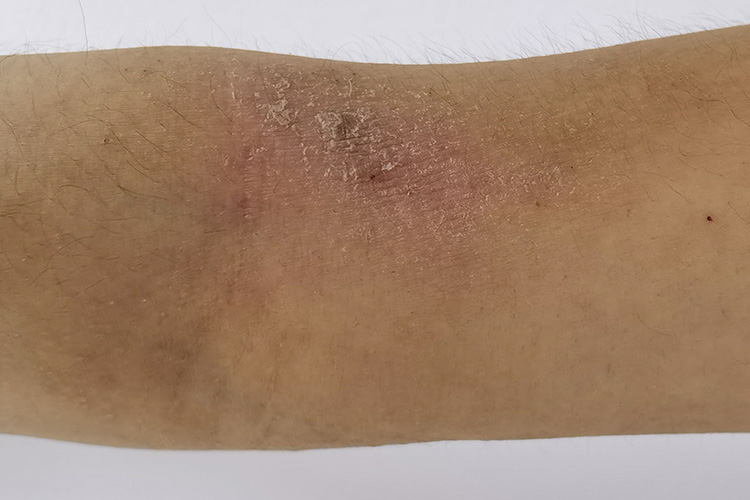

干性湿疹典型症状是皮脂减少、脱屑、皮肤干燥,并伴有不同程度的瘙痒。

干性湿疹的患者会出现皮肤干燥、干裂伴脱屑、皲裂、潮红,触之有粗糙感,并伴有不同程度的瘙痒,由于瘙痒还会出现抓痕和血痂。另外,可能还会出现细裂纹表现,呈淡红色,类似于“碎瓷”。其多发生在冬季,夏季好转,但最终会长期性的出现,并发生明显的湿疹样改变。